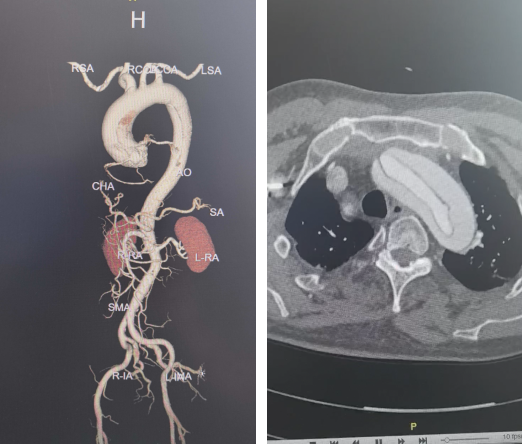

近日,哈尔滨医科大学附属第一医院心脏大血管外科谢宝栋教授团队成功为一名73岁急性Stanford A型主动脉夹层患者,植入了双分支型主动脉术中支架系统。该手术是全国范围内该型支架的首例临床应用,也为高龄急诊主动脉夹层患者提供了新的治疗选择。

患者为73岁男性,因急性主动脉夹层入院。术前检查显示,夹层范围广泛,累及升主动脉、主动脉弓、降主动脉直至腹主动脉,并波及多支重要分支血管,手术复杂度高。

在充分评估后,手术团队决定在传统标准升主动脉置换及全弓重建术式框架下,联合应用双分支型术中支架系统,以实现弓部及降主动脉的同步重建,从而在保证治疗完整性的同时优化整体手术流程。术中植入双分支术中支架系统,并将人工血管远端嵌套至支架近端人工血管内完成连接固定。恢复循环后心脏顺利复跳,完成无名动脉吻合并逐步复温,最终顺利停机,手术过程整体平稳。